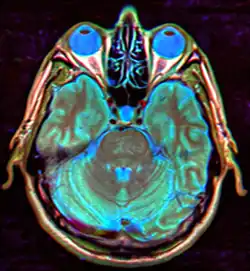

- МРТ головы.

В современных реалиях магнитно-резонансная томография (МРТ) является безопасным и высокочувствительным методом визуализации хиазмально-селлярной области[22][23][24]. Данный метод позволяет проводить исследования в любой плоскости тонкими срезами в 1—1,5 мм, обладает высоким тканевым контрастом, отсутствием артефактов от костных структур черепа.

Для «пустого турецкого седла» характерна триада симптомов:

- наличие цереброспинальной жидкости в полости турецкого седла, о чём свидетельствуют зоны однородного низкоинтенсивного сигнала в режиме T1w и высокоинтенсивного сигнала в режиме T2w, гипофиз при этом деформирован, имеет форму серпа или полулуния толщиной до 2—4 мм, ткань его изоинтенсивна белому веществу мозга, воронка, как правило, расположена центрально;

- асимметричное пролабирование супраселлярной цистерны в полость седла, смещении воронки кпереди, кзади или латерально;

- истончение и удлинение воронки гипофиза.

Помимо основных изменений в параселлярной области МРТ позволяет выявить косвенные признаки внутричерепной гипертензии (расширение желудочков и ликворосодержащих пространств), сопутствующие этой патологии. Разные авторы приводят данные о почти 100 % чувствительности МРТ в диагностике синдрома «пустого» турецкого седла[20][22][23][33].